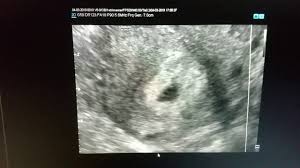

La 5 saptamani de gestatie, embrionul are aproximativ 5 mm, iar inima, creierul si coloana vertebrala se dezvolta constant. Dezvoltarea copilului in saptamana 5 de sarcina. Interviu cu anna smolnițchi despre a treia sarcină, nașterea în picioare și conceperea unui copil.

In aceasta saptamana dimensiunea fatului este intre 2 si 5 mm.